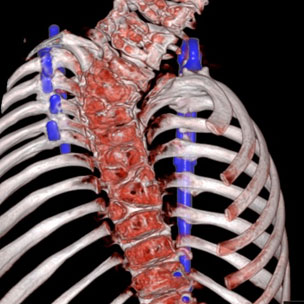

Using Data-Driven, Principled Negotiation with a Clinician-Integrated Approach to Achieve Best Values on Spinal Implants

Quality, Safety and Value (QSVI)